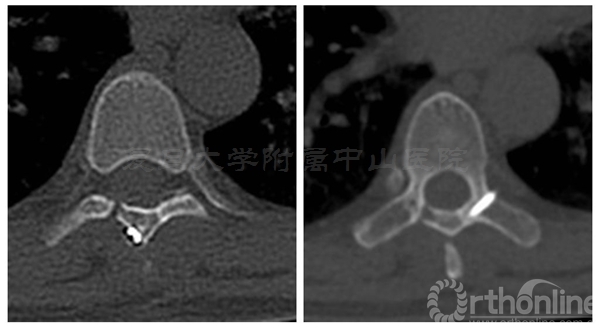

术前三维CT:T7/8水平可见椎管内占位

术中椎板截骨行肿瘤切除后,椎板回植术,回植椎板采用空心螺钉固定

术后肌力恢复至4+级,无脑脊液漏,X线片及CT平扫显示椎板回植位置满意,空心钉固定牢靠。术后病理诊断为脊膜瘤伴细胞丰富